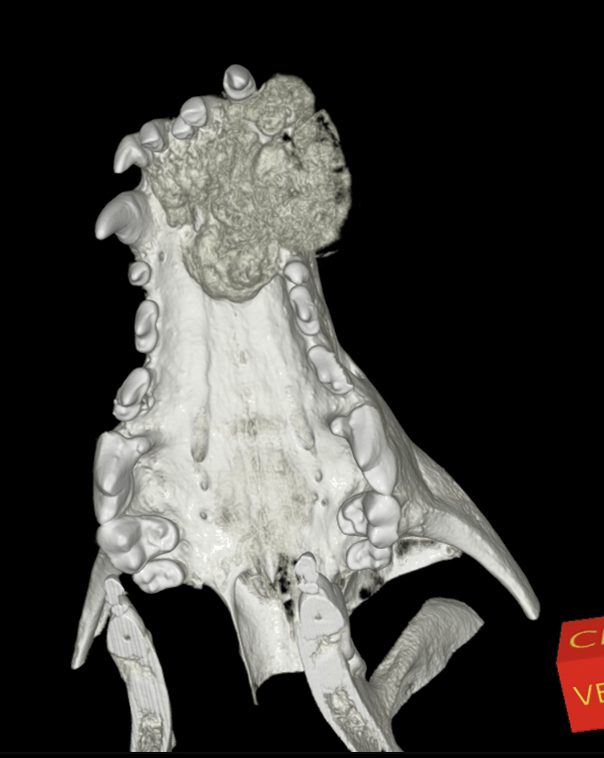

Wegen der klinisch sichtbaren Progression erfolgte die erneute Vorstellung zur weiterführenden Bildgebung. Die durchgeführte CBCT-Untersuchung zeigte eine große, heterogene, überwiegend osteoproduktive Masse des vorderen Oberkiefers. Der Tumor infiltrierte die linke Nasenhöhle, überschritt die Mittellinie und führte zu ausgeprägten knöchernen Destruktionen mit Verlagerung der Schneidezähne. Hinweise auf eine pulmonale Metastasierung ergaben sich in der Thoraxdiagnostik nicht. Das präoperative klinische Staging wurde als Stadium III (T3b, N0, M0) eingestuft. Trotz der ungünstigen Befundlage wurde nach ausführlicher Aufklärung der Besitzer eine operative Therapie angestrebt.